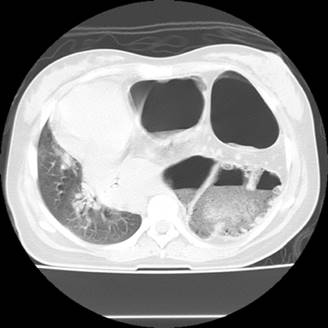

Cuadro de una semana con presencia de dificultad para respirar; tipo progresivo, posteriormente se agrega saciedad temprana e intolerancia a la vía oral con presencia de cuatro vómitos al día de contenido gastroalimentario, acude a hospital donde realiza revisión clínica y se documenta tomografía axial computarizada simple de abdomen, en la imagen digital y cortes axiales se observa presencia de asas de intestino grueso, niveles hidroaéreos en hemitórax izquierdo con atelectasia pulmonar total izquierda, desplazamiento contralateral de todas las estructuras mediastinales (Figuras 1 y 2). Por lo que se refiere a nuestra unidad, se ingresa a la Unidad de Cuidados Intensivos Obstétricos por la presencia de insuficiencia respiratoria, hipokalemia severa e intolerancia a la vía oral, por lo que se decide manejo de vía aérea, y posteriormente se pasa a quirófano para manejo quirúrgico por la presencia de oclusión intestinal. En quirófano se realiza hemicolectomía derecha por la presencia de isquemia y necrosis de pared del ciego y microperforaciones más plastia diafragmática posterior izquierda de aproximadamente 8 cm2 (Figura 3), posteriormente con colocación de sonda endopleural, presentando reexpansión pulmonar, con una evolución satisfactoria para el binomio hasta su egreso de la Unidad de Cuidados Intensivos Obstétricos.

Figura 2: Tomografía axial computarizada con tres asas de intestino grueso ocupando todo el hemitórax izquierdo, con componente liquido aire en su interior, con colapso pulmonar total, y desplazamiento contralateral de todos los órganos mediastinales.